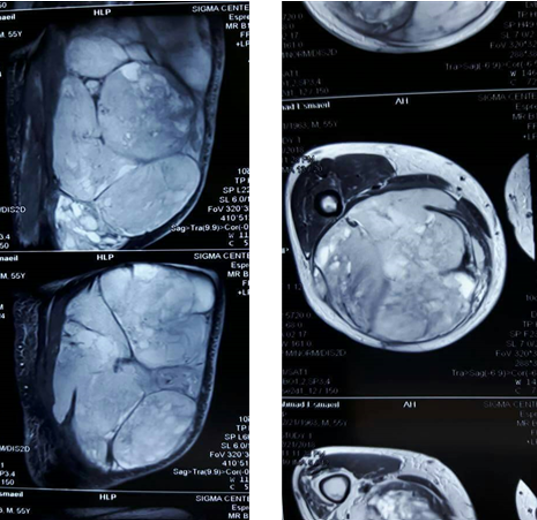

The ultrasound study showed an inconsistent without obvious boundaries mass with peripheral vascularization in the right thigh with an edema in the subcutaneous tissue and a free fluid in the presence of a large mass with areas of necrosis. The mass measured (35x20x18) cm and was located in the posteromedial aspect of the thigh extending from the lower border of the pelvis to the level of fatty lobules. Magnetic Resonance Imaging (MRI) of the right thigh revealed the popliteal fossa which invaded the adjacent soft tissues and had a high signal on T1 weighted and STIR images (Figure 3).

(Figure 3) MRI of the mass revealed a large mass invading the adjacent soft tissue.

The femur was normal with no obvious invasion by the mass. The femoral neurovascular bundle was not affected whereas the sciatic nerve was included in the mass (Figure 3). A Whole-body Computed Tomography (CT) scan revealed no metastases. A bone scan showed an area of irregular increased radioisotope uptake in the middle of right thigh. An excisional biopsy was scheduled and the histopathology demonstrated high grade sarcoma with massive necrosis 60% and the differential diagnosis was: Liposarcoma, Malignant Fibrous Histiocytoma (MFH). The decision was made to resect the mass radically with the possibility of amputation. According to patient’s preference we perform a limb salvage surgery with beforehand knowledge of the occurrence of foot drop. We chose a posterior approach of the thigh, then we dissected it from the muscles and neurovascular bundle and resected it. The sciatic nerve was identified at the greater sciatic foramen, and it was included within the mass. We performed a wide resection of the muscles in the posterior compartment of the thigh including parts of semitendinosus, semimembranosus and Biceps Femoris muscles. The sciatic nerve was resected from the greater foramen to the popliteal fossa. The resected mass weighed about 25 kilograms (Figure 4).